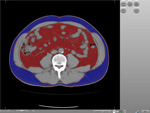

■ 体脂肪測定ソフト

ZIOSTATIONのオプションに「体脂肪測定ソフト」が加わりました。

データを開き、測定したいスライス上でマウスを1クリックするだけの簡単操作で体脂肪を測定できます。測定結果は1クリックでレポートに出力可能。ルーチンのメタボリック症候群の検診を支援します。

体脂肪測定ソフト